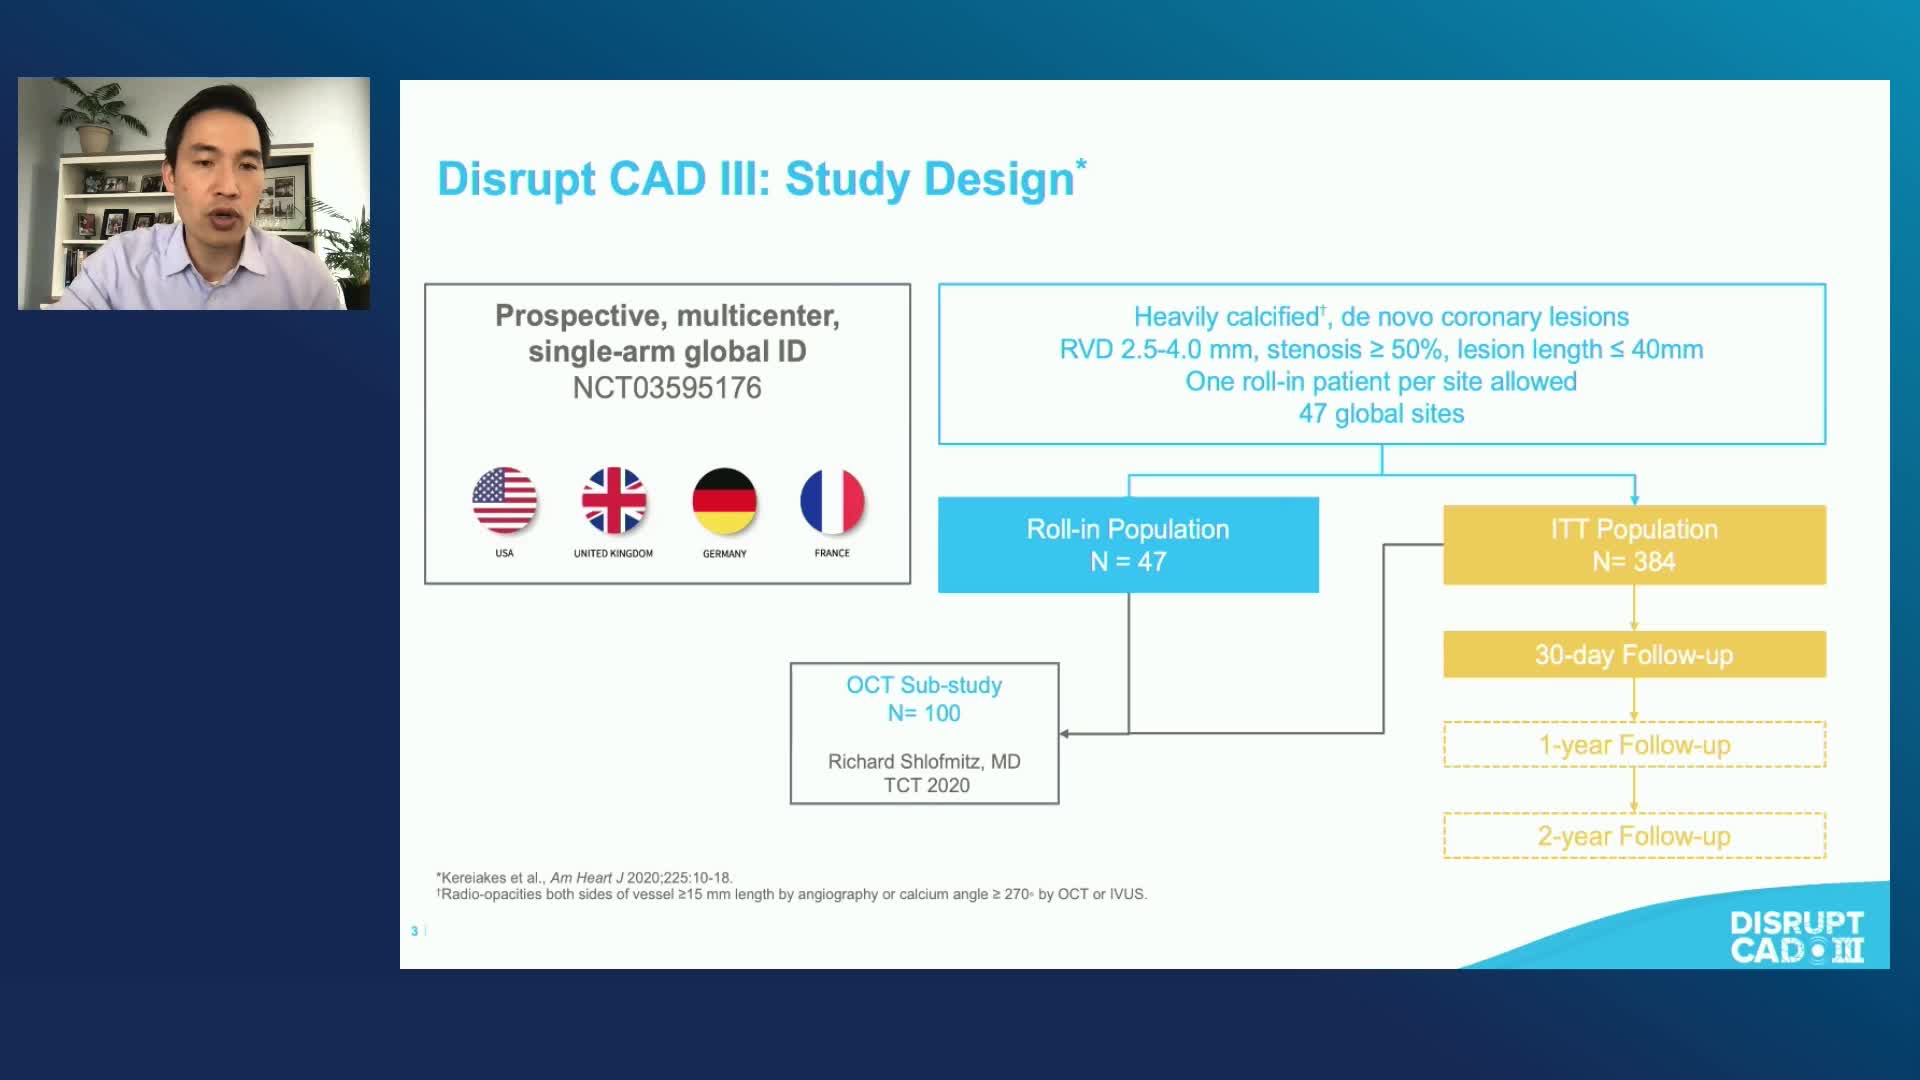

Intravascular Lithotripsy for Treatment of Severely Calcified Coronary Artery Disease: The Disrupt CAD III Study